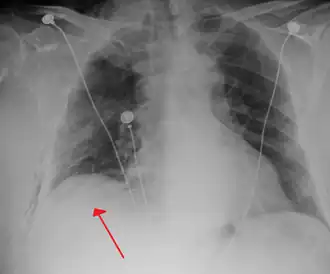

Image from a computed tomography (CT) scan of the chest. On the right (left side of the patient) there is a black area suggesting free air inside the chest

CT scan of the chest showing a pneumothorax on the person's left side (right side on the image). A chest tube is in place (small black mark on the right side of the image), the air-filled pleural cavity (black) and ribs (white) can be seen. The heart can be seen in the center.

The thoracic cavity is the space inside the chest that contains the lungs, heart, and numerous major blood vessels. On each side of the cavity, a pleural membrane covers the surface of lung (visceral pleura) and also lines the inside of the chest wall (parietal pleura). Normally, the two layers are separated by a small amount of lubricating serous fluid. The lungs are fully inflated within the cavity because the pressure inside the airways (intrapulmonary pressure) is higher than the pressure inside the pleural space (intrapleural pressure). Despite the low pressure in the pleural space, air does not enter it because there are no natural connections to air-containing passages, and the pressure of gases in the bloodstream is too low for them to be forced into the pleural space.[16] Therefore, a pneumothorax can only develop if air is allowed to enter, through damage to the chest wall or to the lung itself, or occasionally because microorganisms in the pleural space produce gas.[16] Once air enters the pleural cavity, the intrapleural pressure increases, resulting in the difference between the intrapulmonary pressure and the intrapleural pressure (defined as the transpulmonary pressure) to equal zero, which cause the lungs to deflate in contrast to a normal transpulmonary pressure of ~4 mm Hg.[33]